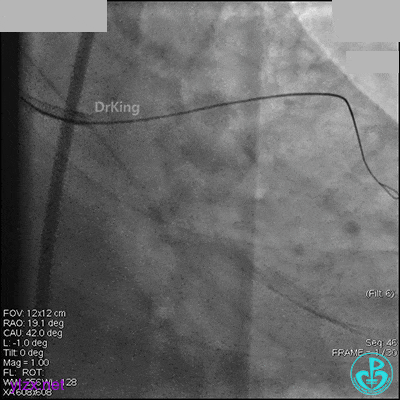

AL 1.0指引导管到位,简单短时尝试导丝不能顺利通过前降支或回旋支病变。改变策略处理右冠脉病变,计划植入2枚支架。AL指引导管到位,Sion blue导丝到达右冠脉远端。导丝通过后1.5mm及2.5mm球囊14~16atm充分扩张中段病变。

右冠脉中段充分扩张后欲植入3.5×38mm支架时,支架难以通过中远段扭曲处,且指引导管、导丝弹出飞扬。反复尝试导丝重新到达右冠脉远端时通过不顺利,局部造影剂滞留,远端血流接近3级。